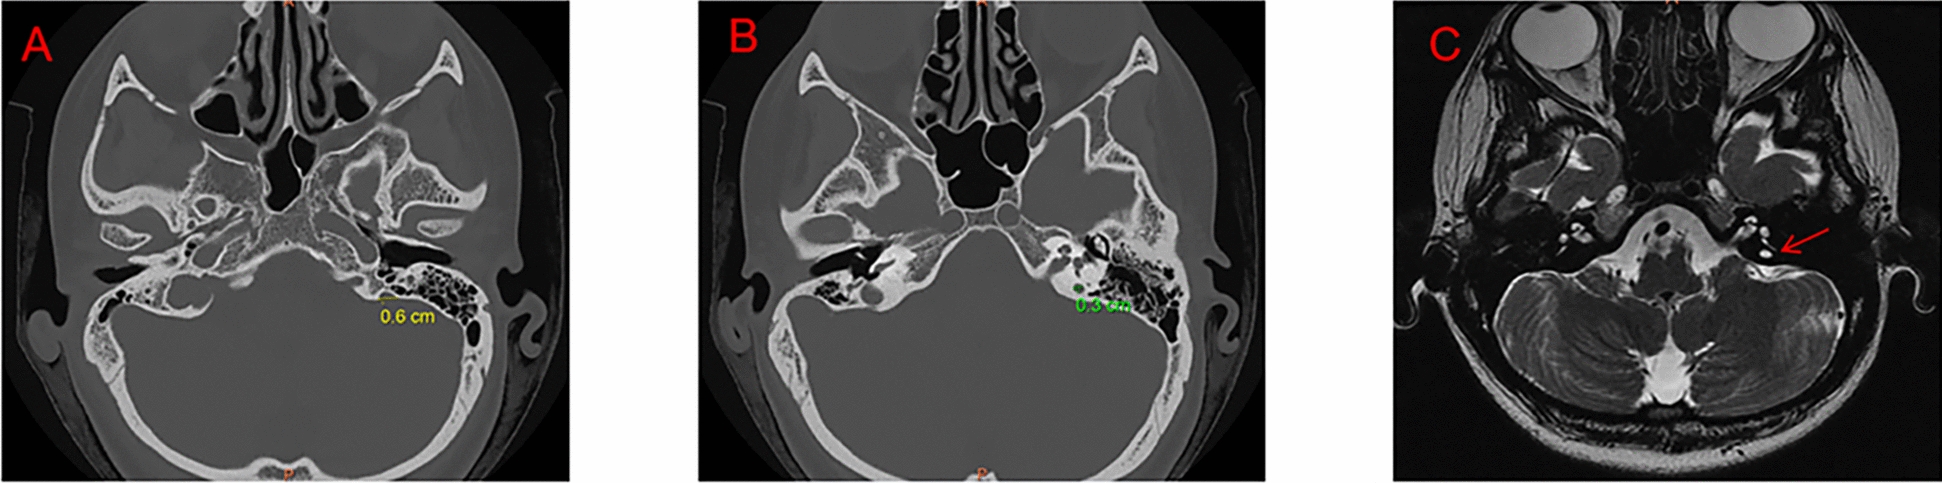

Case presentation: A 20-year-old Han Chinese female presented with bilateral preauricular and lateral neck fistulas since birth, accompanied by intermittent discharge. Physical examination revealed cup-shaped right ear deformity, bilateral preauricular fistulas, and branchial fistulas. Audiometry showed bilateral sensorineural hearing loss. Imaging studies identified an enlarged vestibular aqueduct and a hypoplastic left kidney. The patient underwent bilateral preauricular fistulotomy and bilateral branchial fistulotomy. Half a year after surgery, the patient's incision healed well with no discharge or signs of recurrence. Unfortunately, the patient did not undergo genetic testing.